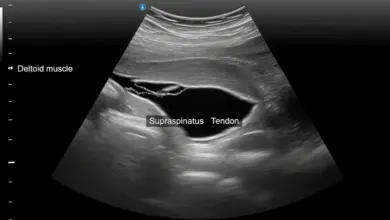

O exame avalia instabilidade, apreensão e padrão de dor, mas a confirmação costuma depender de ressonância magnética, muitas vezes com artrografia (contraste intra-articular), que melhora a visualização capsuloligamentar.

Nem sempre. Em alguns casos, a artro-ressonância melhora a visualização da cápsula e do ligamento. A correlação com exame físico e história é decisiva.